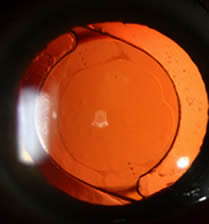

What Is a Cataract ?

A cataract is a clouding of the lens of your eye. With increasing age, proteins in your lens begin to break down and the lens becomes cloudy. You may not even realize you have a cataract because it usually grows very slowly and may not impede vision early on. While cataracts are rarely dangerous, after a number of years they will likely affect vision. . A cataract is not caused by overuse of your eyes and it does not travel from one eye to the other.

Cataracts can be diagnosed by your eye doctor during a dilated eye exam. You may also have your vision checked in different lighting conditions and with an updated glasses prescription. A complete eye exam is necessary to determine if anything else is contributing to your visual symptoms.